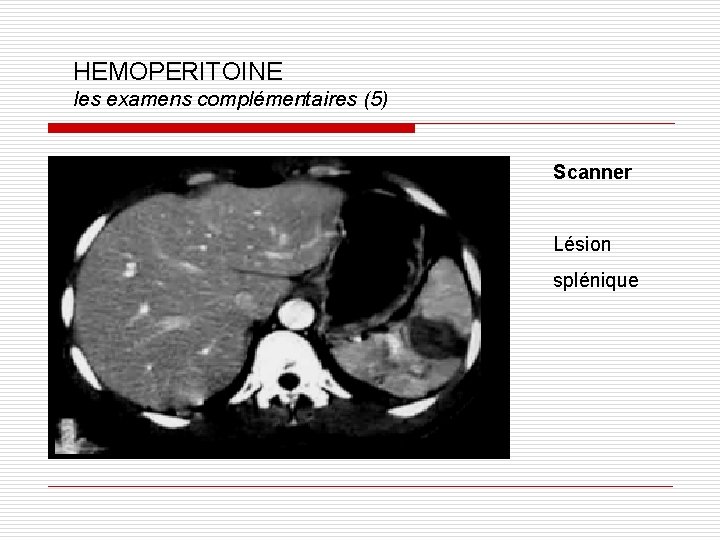

HEMOPERITOINE les examens complémentaires (5) Scanner Lésion splénique